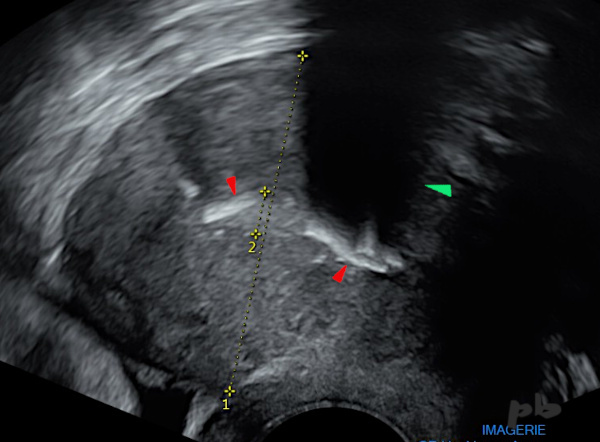

(même patiente que 16)

Echographie réalisée 9 mois après l’HSG. Antécédent de curetage.

Apparition d’une volumineuse calcification (►) avec cône d’ombre (►).